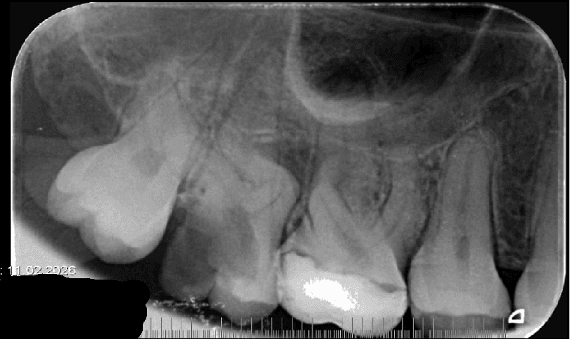

Hastanın klinik muayenesinde 17 numaralı dişte koronal yapıyı ciddi şekilde etkileyen madde kaybı ve kırık hattı gözlemlenmiştir. Alınan pre-operatif periapikal radyografide, kök kanal anatomisinin oldukça kompleks olduğu ve köklerde keskin bir kurvatür bulunduğu tespit edilmiştir. Mevcut koronal harabiyet ve pulpal durum göz önüne alınarak dişe kök kanal tedavisi endikasyonu konulmuştur.

Kanal Dolumu: Şekillendirme ve final irigasyonunu takiben kanallar kurutulmuş ve tek seansta sızdırmaz bir şekilde üç boyutlu obturasyon işlemi gerçekleştirilmiştir. Alınan radyografilerde aşırı kurvatürlü kanalların orijinal anatomisine sadık kalındığı görülmektedir.